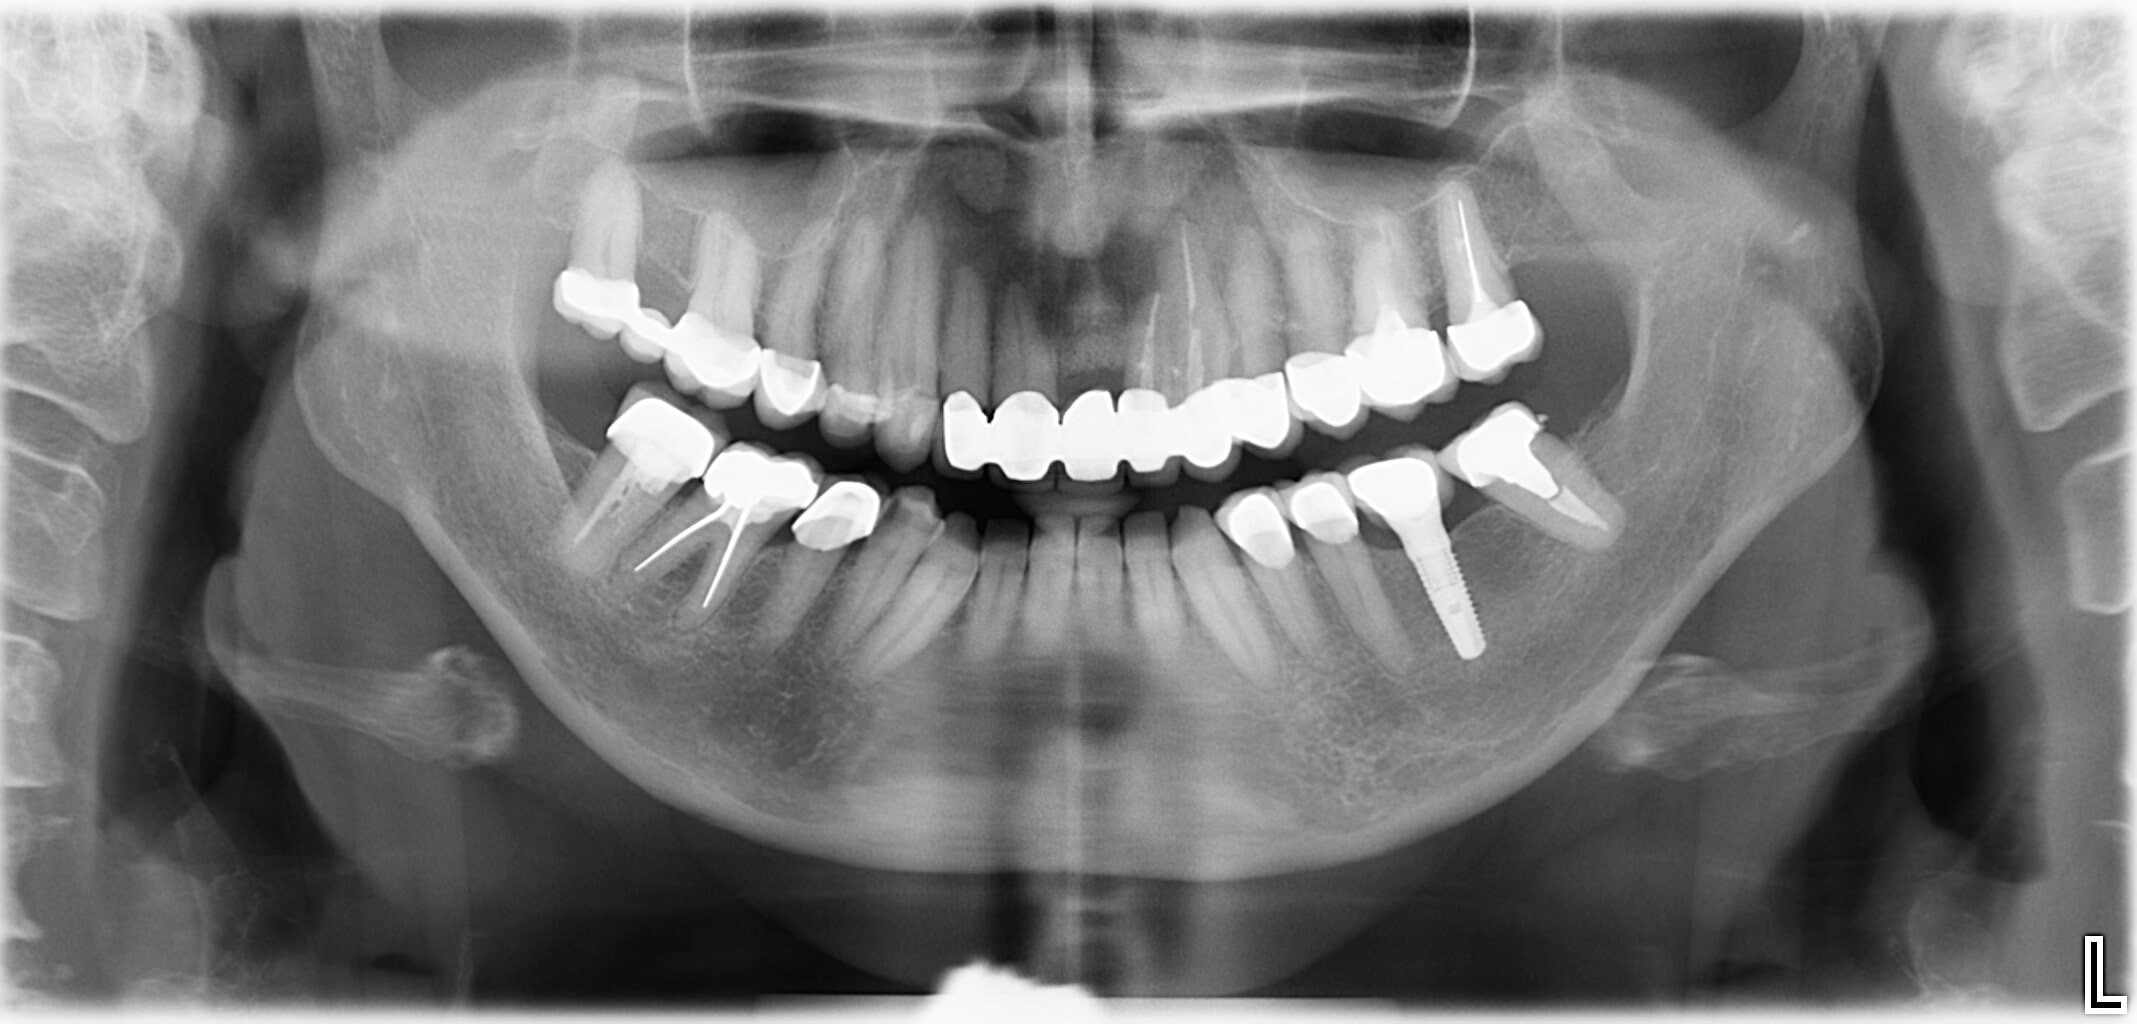

Wenn bei einer unvollständigen Zahnreihe nur ein oder zwei Zähne fehlen, sind meist Implantate die richtige Lösung.

Bei einer Implantation werden künstliche Zahnwurzeln eingepflanzt. Daran können Zahnkronen befestigt werden. Ein Beschleifen der Nachbarzähne (wie es bei herkömmlichen Brücken oft nötig ist) ist dabei nicht notwendig.

- Implantatgetragener Zahnersatz anstelle einer Brücke oder herausnehmbarer Teilprothese

- Fehlende Zähne werden Zahn-für-Zahn mit Implantaten ersetzt